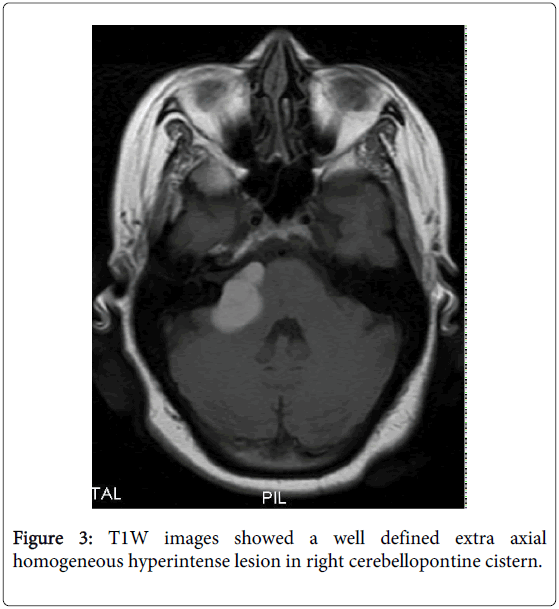

Unusual CT and MRI? Appearance** of an Epidermoid Cyst: A Case Report